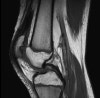

MRI도 진단에는 큰 도움이 되지 않으며 다른 병이 있는지 찾아내는데 도움이 됩니다.

MRI : 연골연화증(Chondromalasia)